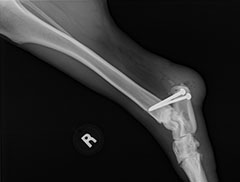

How To Beat Achilles Tendinitis. Discomfort in the Achilles and heel region is a common clinical discussion especially in individuals involved in repeated weight bearing activity such as extreme walking, jumping or running sports. If not captured early this can be a tough injury to cure but with the ideal treatment and particularly eccentric strengthening workouts a full recuperation can generally be accomplished. It is very important to be patient and not return too soon to sports and activities that stress the tendon. I have actually been doing the heel-drops for over 6 weeks and I'm still experiencing some discomfort in my left achilles. It is most likely that your plantar fascia is inflamed and it is necessary that you rest your afflicted foot by raising it if your pain is extreme. You should likewise ice it by rubbing a frozen bottle of water beneath the heel and arch for several minutes whenever the discomfort is intense. Surgery is hardly ever suggested unless the Achilles tendonitis is persistent and particularly severe, or if the tendon has actually ruptured totally. While you are dealing with the damage to the tendon fibers through eccentric heel drops, there are some actions you can require to assist ameliorate a few of the other contributing factors to your injury. So simply to say if you have insertional achilles tendonitis see a Podiatric doctor - just to obtain another viewpoint. If you remain to train on it, the discomfort in the tendon will be more sharp and you will feel it more often, eventually impeding your ability even to jog gently. I took a full year off of running the last time, yet I still can't run more than two times a week (12 miles total, tops) for fear of it returning complete fledged. There will be a progressive beginning of Achilles tendon pain over a duration of weeks, or perhaps months. Some shoes can also put pressure on the back of your heel, irritating the insertion of the tendon. This workout is used for cases of insertional Achilles tendonitis, replacing workouts 1 & 2. Like the exercises for midpoint Achilles tendonitis, utilize the opposite leg to go back to the up" position and include weight once you can do it pain-free. I believe the Stairmaster provides a focused conditioning of the muscles in the calves, and also duplicates some of the positive aspects of eccentric heel drop treatment. Utilize the modified flat eccentric heel drop exercise instead of the two variations off an action if you have insertional Achilles tendonitis.